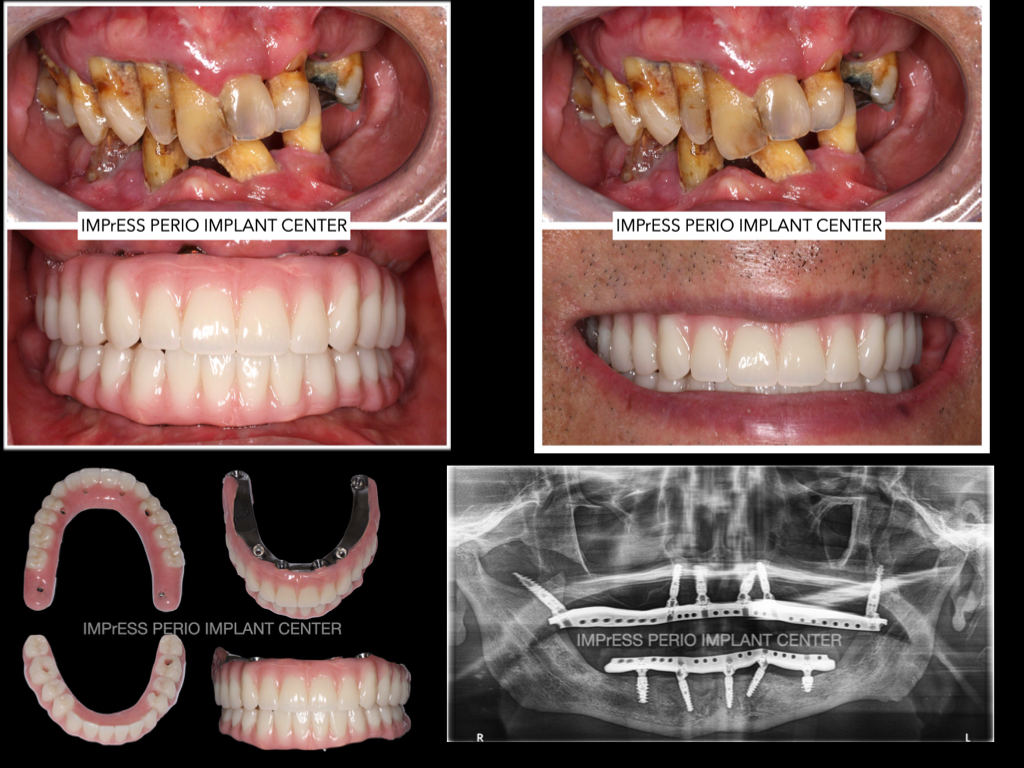

All On X Full Mouth Implants Fixed Teeth IMPrESS Perio Implant Centre Dr Noroozi Burnaby Vancouver BC

A Solution for Sever Bone Loss Patients

Patients who suffer from severe bone loss are typically told they do not have enough bone for traditional dental implant surgery. With Pterygoid and Zygomatic implants, the impossible is now possible, and patients can benefit from enjoying their life with permanent teeth secured by implants.

A minimally invasive solution with a fixed full-arch implant restoration for high patient satisfaction, Fixed (Non-removable) Same-Day-Teeth, providing immediate function and aesthetics